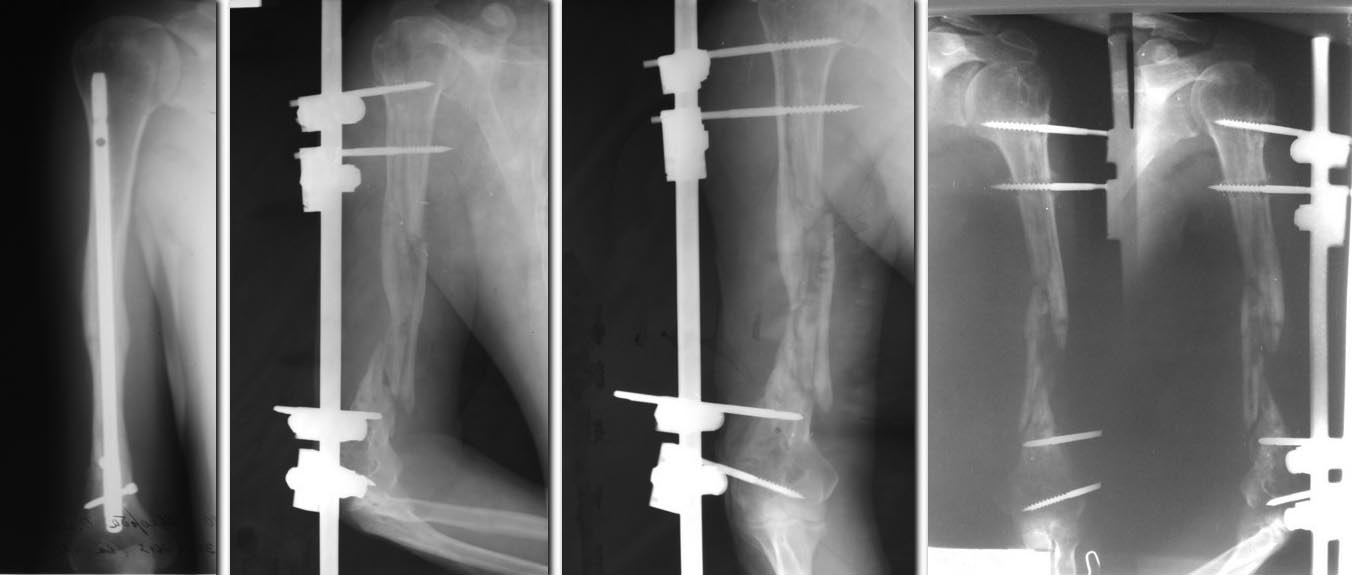

В моем архиве есть похожее наблюдение. Пациентка перенесла накостный остеосинтез плеча 20 лет назад. Сращения не наступило, но она к врачам не обращалась. При обследовании у нас обнаружен ложный сустав с деформацией плечевой кости в виде коньячного бокала дистального фрагмента в котором помещалась пластина, фиксированная на проксимальном фрагменте. На операции после удаления костных разрастаний сформировался дефект плечевой кости, похожий на Ваш случай.Был выполнен интрамедуллярный остеосинтез стержнем с угловой стабильностью винтов. Костный дефект заполнен свободными костными аутотрансплантатами из крыла подвздошной кости (брали с обеих сторон). Каждый трансплантат был разделен пополам поперек, а каждый фрагмент расщеплен вдоль.Далее фрагменты уложены в дефект, как черепица и фиксированы серкляжными швами. Через год мы получили ложный сустав на двух уровнях и патологическую подвижность на стержне. Промежуточный фрагмент представлял собой достаточно полноценную кость. Повторная операция заключалась в удалении металлоконструкций с последующим накостным остеосинтезом реконструктивной пластиной (фирмы Деост) из заднего доступа с адаптацией всех фрагментов кости. Костная пластика зоны проксимального ложного сустава выполнена несвободным костным трансплантатом из наружного края лопатки, на дистальном уровне выполнена костная пластика аллотрансплантатом. Через 4 месяца отмечена консолидация.

В Вашем случае можно начать лечение пациента с накостного остеосинтеза пластиной (Деост)из заднего доступа с костной аутопластикой свободным трансплантатом из гребня,хотя бы для создания костной массы (и с надеждой на сращение). Кроме названной пластины дистальный фрагмент плеча ни что не удержит из за его малых размеров. Если сращения не наступит, то при следующей операции, можно использовать несвободный костный трансплантат на лучевой артерии с предплечья. Лопатка в качестве костного донора не годится из за короткой ножки. Положительных результатов при использовании свободных кровоснабжаемых трансплантатов из малоберцовой кости у меня не было. Иллюстрации могу послать на Ваш электронный адрес, их достаточно много и они много весят.

Большое спасибо за ответ и фото. Позволю себе выложить их здесь.

1 до операции

1а до операции

2 до операции

3 схема вид отломков после удаления пластины

4 вид отломков после удаления части стенки "бокала"

5 вид отломков при сохранении одной из стенок

6 остеосинтез стержнем

7 схема укладки трансплантатов

8 фото момент укладки трансплантатов в дефект

9 контрольная рентгенограмма после операции

10 рентгенограмма через год

11 остеосинтез пластиной с костной пластиной

(спицы слева от пластины фиксируют тр-т из лопатки)

12 пластина

13 рентгенограмма через год

14 клинически через год (может и выше)

|